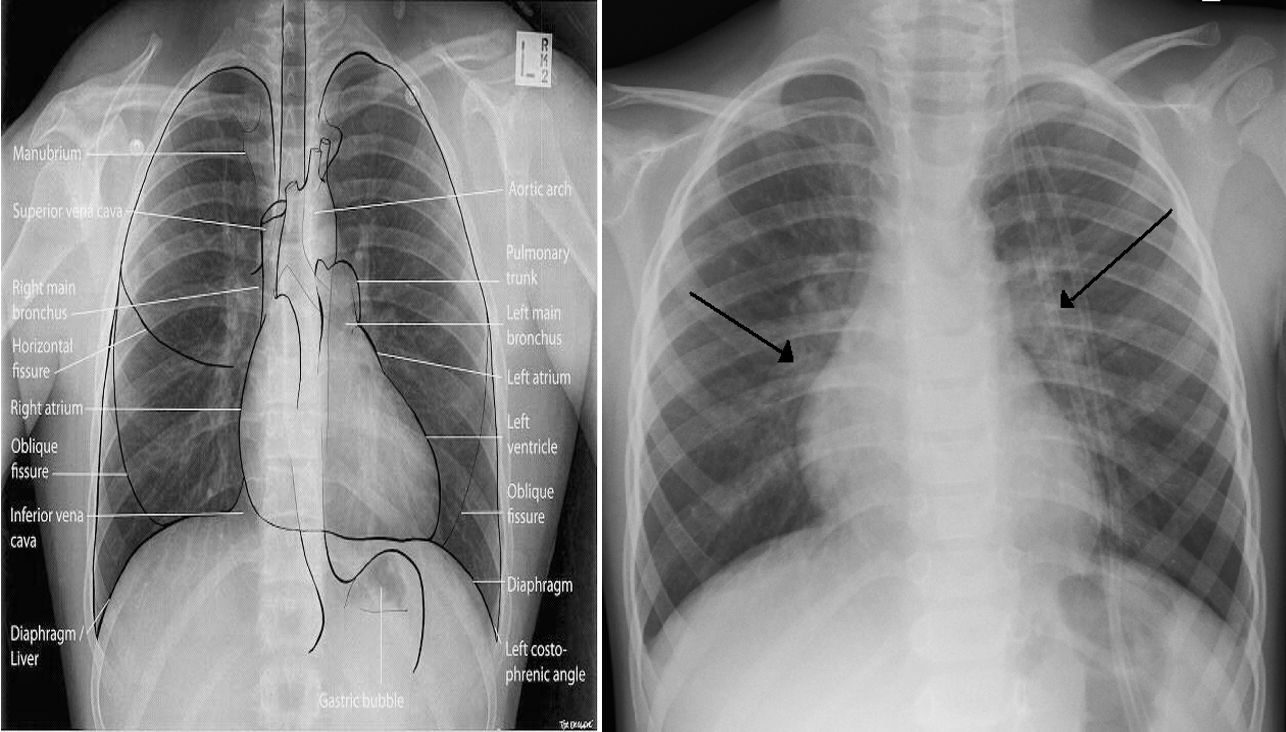

X-ray finding

- Hyperinflated lungs.

- In 30% scattered areas of opacity due to consolidation or atelectasis.

- An X-ray of a child with RSV showing the typical bilateral perihilar fullness of bronchiolitis.